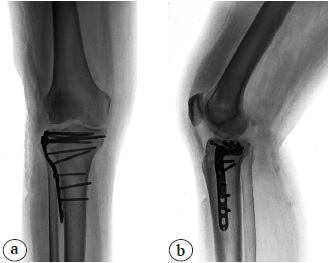

На 13-е сут. после повторной ревизии, дебридмента и ушивания раны сняты швы, пациентка выписана на амбулаторное лечение под наблюдение травматолога поликлиники с рекомендациями по ограничению осевой нагрузки на правую нижнюю конечность и ношению ортеза правого коленного сустава. На контрольных рентгенограммах, выполненных в это время, признаки нестабильности имплантатов отсутствовали (рис. 4). Пациентка получала антибактериальную терапию широкого спектра (Цефтриаксон 1,0 г 2 раза в день), которая была начата в день первичной ревизии раны. Посев отделяемого из раны выявил рост S. aureus, устойчивого к бензилпенициллину, но чувствительного к большинству антибиотиков широкого спектра, в том числе цефалоспоринам III поколения. Однако, учитывая положительную динамику в ране и купирование воспалительного процесса, продленная этиотропная антибактериальная терапия не назначалась.

Рис. 4. Отсутствие признаков нестабильности имплантатов на контрольных рентгенограммах после купирования первичного инфекционного процесса, перед выпиской: a — прямая проекция; b — боковая проекция

Fig. 4. Absence of implant instability signs in control x-rays after resolution of primary infectious process, before discharge: a — AP view; b — lateral view